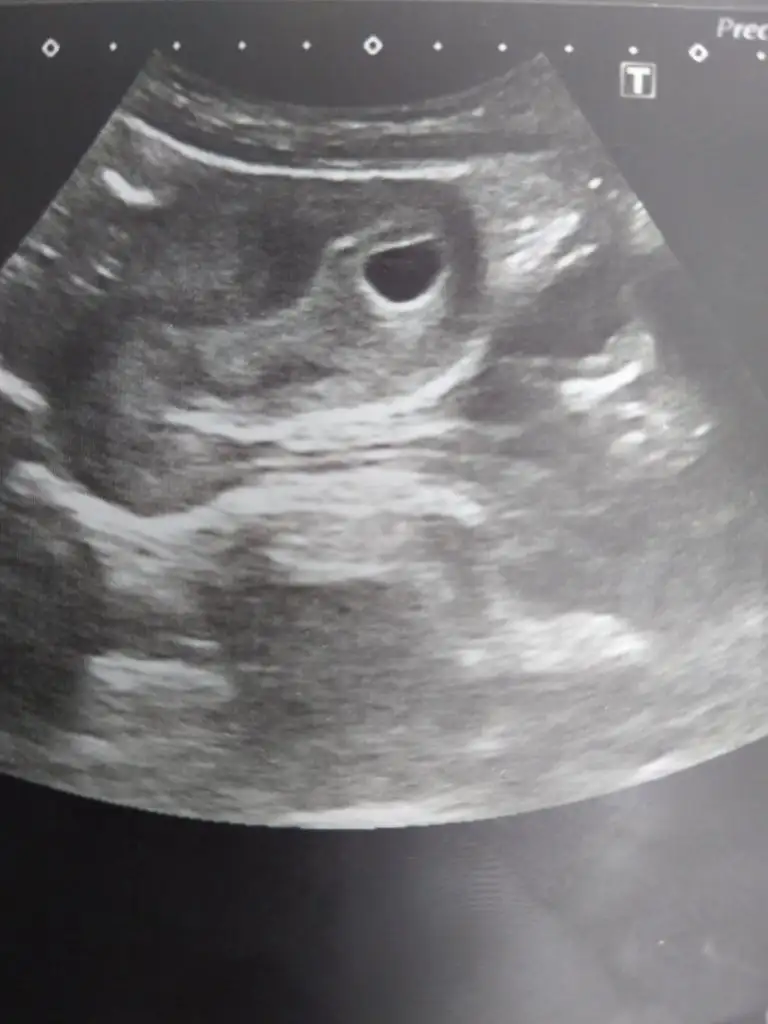

Merhaba arkadaşlar dün doktora gittim beta 29 binlerde kese var bebek görünmüyor doktor kontrol etti tam 6 haftalik dedi niye görünmedi vs hicbisi demedi endişeleniyorum bende şimdi arastirdigim da 6 haftalik kalp atışı duyulur diyorlar bizde neden böyle ultrason fotoğrafınıda yuklesem yardımcı olsaniz

Doktor hersey iyi dedi sorun yok demi dedim yok dedi devlet hastanesine gittim hasta çok Bi hastaya 1 dk anca bakıyor hemen oldu bitti yarın kan sonuçlarını bakicak dedi vitaminlerini düzenlerizN nurrr256 uzaktan boş gibi, yaklaşınca sanki sol üstte yolk kesesi belirsiz var gibi çok anlamadım, 6 haftalık ise kalp atışı duyulmayabilir ama yolk kesesi olması lazım diye biliyorum, doktor ne dedi haftaya gel bakalım mı dedi? doktor bir şey demediğine göre bence normaldir, yoksa boş gebelik derdi sanırım, kafana takma bekle bakalım belki cihazla ilgilidir.